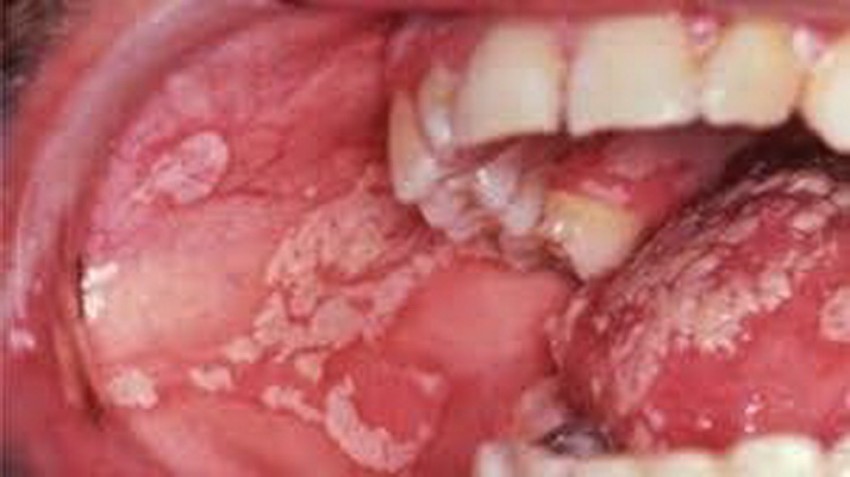

Bệnh nấm miệng thường gặp ở trẻ nhỏ, người cao tuổi và những người mắc nhiều bệnh nền, sức đề kháng yếu. Có nhiều nguyên nhân gây bệnh nấm miệng nhưng căn nguyên chính vẫn là do miễn dịch kém. Bệnh nấm miệng hình thành nên các đốm màu trắng hoặc vàng trên bề mặt lưỡi hoặc má trong, họng và chảy máu khi bị cạo ra. Những đốm này thường biến mất nếu được điều trị đúng cách.

Ở giai đoạn đầu, nấm miệng không có triệu chứng. Nhưng ở giai đoạn nặng hơn, bệnh nhân có thể gặp phải những triệu chứng như sau: Xuất hiện các vạt trắng hoặc vàng nhạt ở má trong, trên bề mặt lưỡi, trong họng, nướu hoặc môi. Chảy máu nếu cào mạnh vào những đốm này. Cảm giác nóng trong miệng, cảm giác như có bông trong miệng, chốc mép, khó nuốt, có vị đắng trong miệng, giảm vị giác. Trong một số trường hợp, nấm miệng còn ảnh hưởng đến thực quản. Loại nấm gây ra bệnh nấm miệng cũng có thể gây nấm ở những bộ phận khác trên cơ thể.